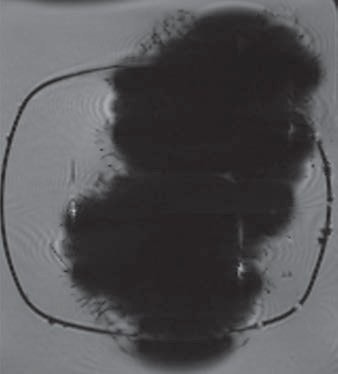

In comparing the MR images, the artifact created from the magnetic eyelashes was much larger than the distortions created by three aneurysm clips. The artifact from the eyelashes measured 7 x 6 cm and was most severe on the susceptibility-weighted imaging sequence.